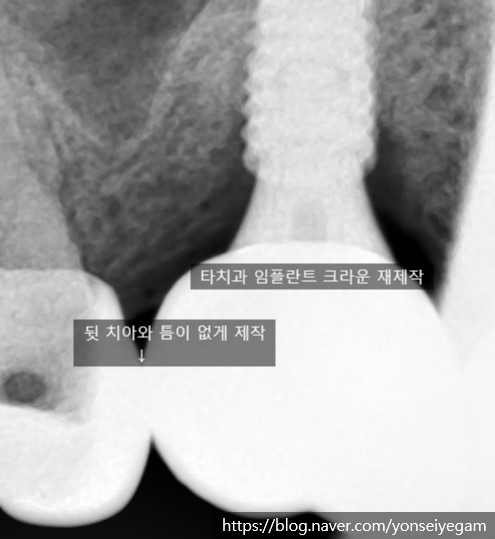

다른 치과에서 오래전에 한 크라운과 임플란트크라운(머리부분) 사이에 치실이 숭숭 빠질 만큼의 틈이 있어 식사할 때마다 음식물이 껴서 불편한 상태였습니다. 이렇게 음식물이 끼어 관리가 안되면 임플란트주변의 뼈들이 소실되어 임플란트에 안좋은 영향을 초래하게 됩니다.

임플란트의 크라운을 치료할 것인지 아니면 뒷치아 크라운을 뜯어내고 치료할 것인지 환자와 상담후에 뒷치아가 예전에 신경치료를 하지 않고 크라운을 한 치아이기 때문에 뒷치아 메탈크라운을 뜯어내고 다시 다듬어 치료할 경우, 시려서 신경치료를 해야될 가능성이 있었고 환자분이 곧 출국해야하여 시간이 없었으므로 임플란트의 크라운을 저희 치과에서 재제작하기로 하였습니다. 임플란트 크라운이 임플란트 중간구조와 붙어있어 중간구조와 분리되지 않는 형태였기 때문에 임플란트 중간 구조도 이번 기회에 같이 교체하였습니다.

치료 전, 뒷치아와 임플란트 크라운 사이에 틈이 있음

치료 후, 그 틈을 없애드렸습니다.

위의 케이스는 완성까지 내원횟수; 2번, 내원 기간; 총 5일

임플란트 크라운 제작을 위한 중간구조물장착과 본 뜨는 과정을 위한 내원 1번과

5일 후 임플란트 크라운 장착을 위한 내원 1번 으로 총 2번 내원으로

몇 년동안의 음식물이 끼는 불편감을 해결하셨습니다.